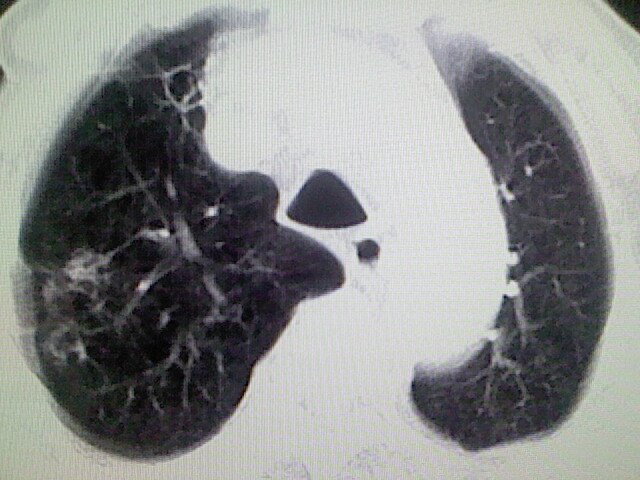

以下是引用zsl6918在2008-8-28 16:49:00的发言:[br]双肺炎性病灶,食管狭窄估计与心房增大压迫所致。

以下是引用xulianj在2008-8-28 20:36:00的发言:[br]慢支肺气肿伴感染,右上肺陈旧性结核;食道建议胃镜检查。

以下是引用wqs571018在2008-8-28 21:18:00的发言:[br]慢支继发感染,右上肺陈旧性结核;食道建议胃镜检查。